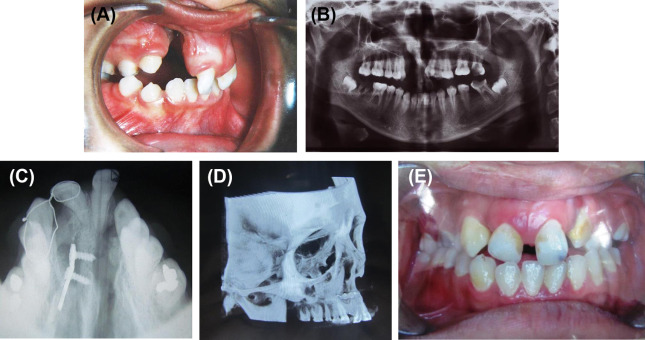

(A) Protruded premaxilla. (B) Orthopantomograph view showing rotated premaxilla. ...

Figure 2.

(A) Protruded premaxilla. (B) Orthopantomograph view showing rotated premaxilla. (C) Occlusal radiograph 3 months after the operation showing appropriate fixation and consolidation of bone graft in the right side. (D) Postoperative cone beam computer tomography (CBCT). (E) Postoperative photograph 3 months after the operation.

The patient was a 22-year-old girl with bilateral cleft lip/palate and protruded premaxilla. There was a large oronasal fistula posterior to the premaxillary segment. The lip had undergone surgery in infancy, but a severe whistle deformity and a visible muscle bulge at the lateral segments were evident. The premaxilla was set back using the above-mentioned procedure and the bone was grafted (unilaterally; Figure 2). Bone grafting on the other side was performed in a separate session. The patient was followed up for 4 years.